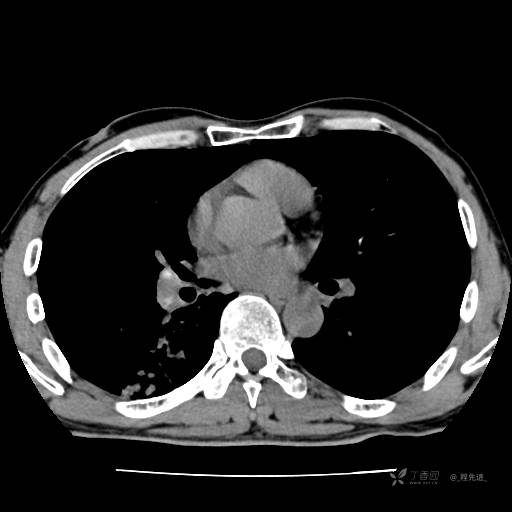

辅助检查:我院门诊胸部CT示:如下。心电图:窦性心律;正常心电图。